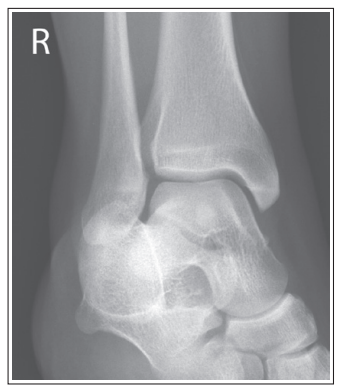

The medial talar dome is demonstrated anterior to the lateral talar dome

Over-rotated/ external rotation

The medial talar dome is demonstrated posterior to the lateral talar dome

Under-rotated/ internal rotation

Medial talar dome is anterior to the lateral dome

Fibula is more posterior

Foot is externally rotated

Medial talor dome is posterior to the lateral dome

Foot is internally rotated